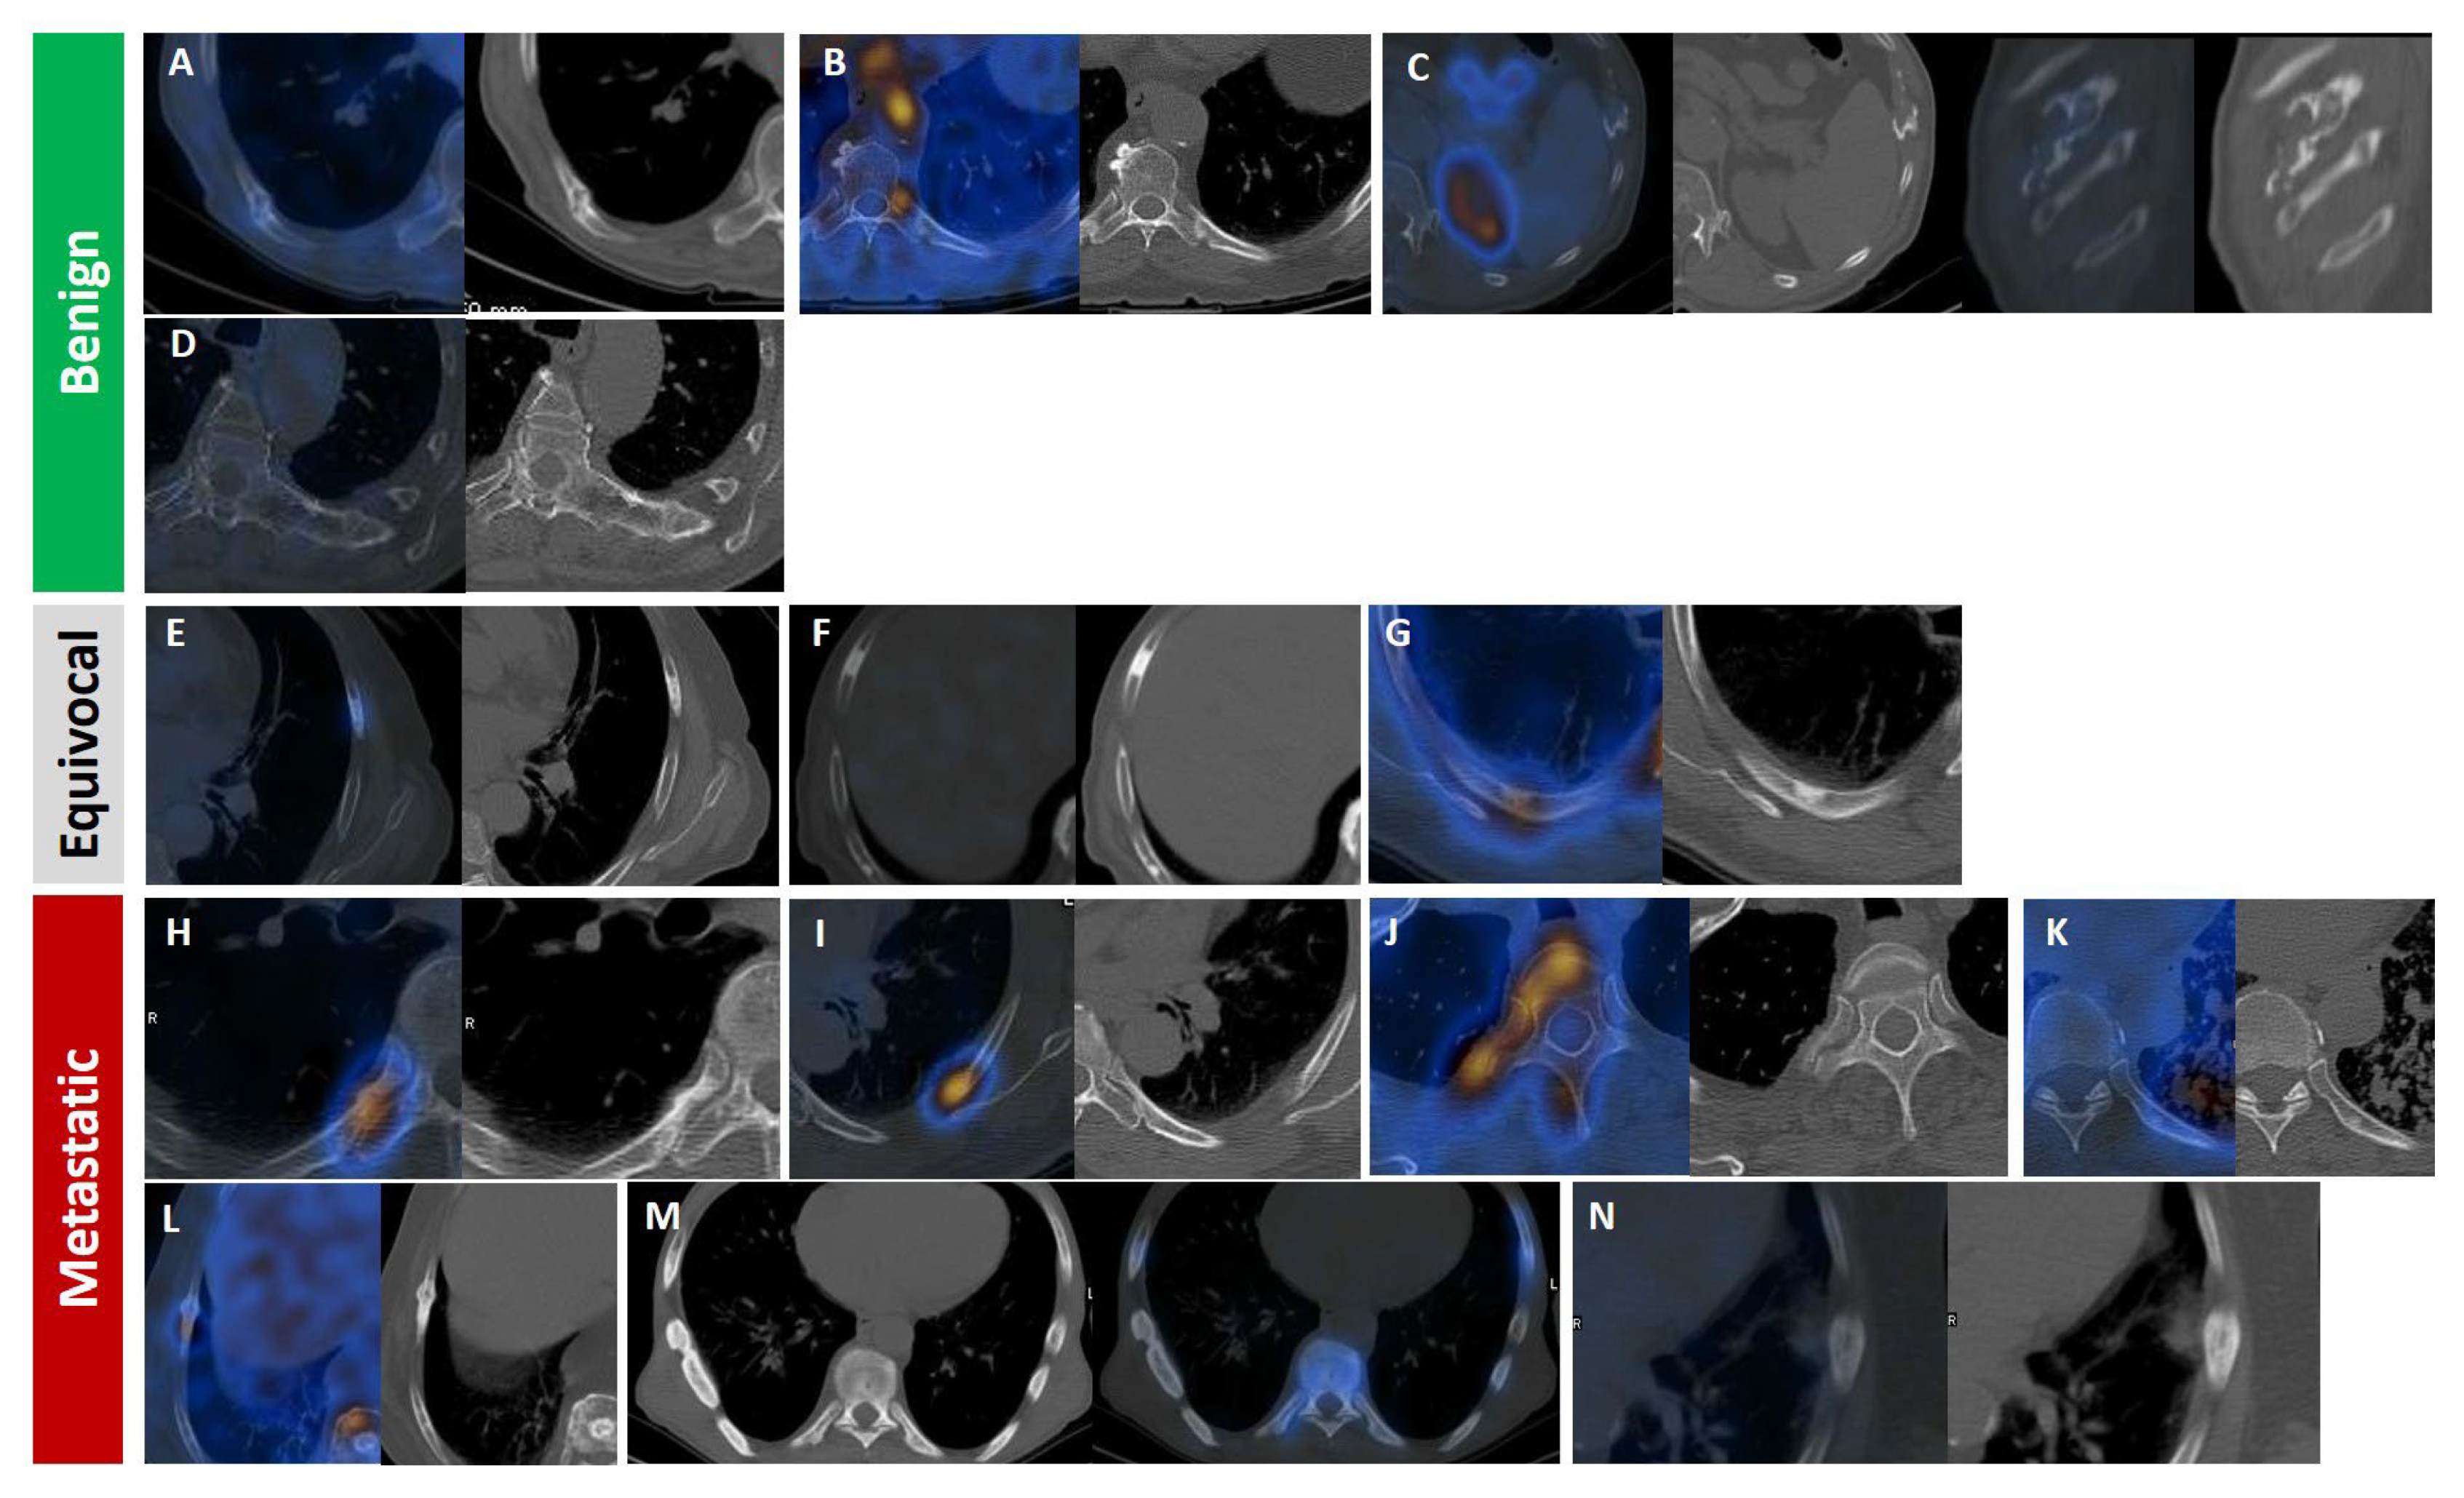

Figure 7.

Radiologic appearance of PSMA-avid rib lesions in prostate cancer patients, categorized by likelihood of malignancy: benign (A–D), equivocal (E–G; all isolated), and malignant (H–N). Fracture line with callus formation and faint PSMA uptake (A). Focal moderate uptake at the costovertebral joint, consistent with degenerative changes (B). Well-defined expansile non-PSMA-avid lytic lesion at the costochondral junction, likely a benign chondroid lesion (C). Left transverse process connected to an adjacent isolated rib (D). Focal lytic–sclerotic lesion anterolaterally with moderate uptake. (F) Focal dense sclerosis without uptake (E). Eccentric/mural focal sclerosis with moderate uptake (G). Focal intense uptake with periosteal reaction and sclerosis at the costovertebral rib portion (H). Focal intense uptake in the posterior rib arc with ground-glass appearance (I). Focal intense uptake with mild sclerosis in the vertebral body extending to head, neck, and posterior rib arc (J). Focal mild uptake with sclerotic changes in posterior arc amid miliary lung metastasis (K). Linear sclerotic lesion showing moderate PSMA uptake and callus formation, indicating pathologic fracture (L). Linear dense sclerotic changes along lateral rib arc with mild PSMA uptake (M). Periosteal reaction with faint PSMA uptake and adjacent soft tissue involvement (N).